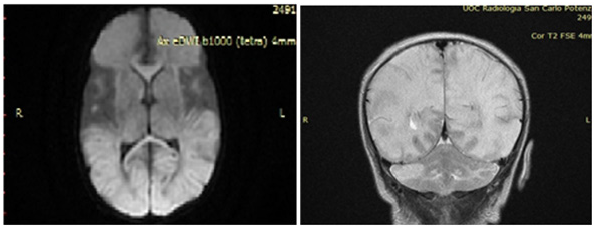

Figure 1: Brain RMI.

Bacterial cultures of specimens collected at the time of admission were negative and also viral investigations on blood, urine, nasopharyngeal swab and stool samples resulted negative for all investigated pathogens (Enteroviruses, HSV1, HSV2, cytomegalovirus, Epstein-Barr virus, human herpesvirus 6, parvovirus B19, adenovirus). A lumbar puncture was also performed, and CSF tested positive for HPeV (by Film Array, but without the possibility of identifying the specific genotype). At that point, acyclovir was stopped and was started Intravenous Immunoglobulin (IVIG) 1gr/kg for 3 days. After 5 days of hospitalization she performs brain MRI (Figure 2), that showed cerebral White Matter (WM) suffering, extended into the subcortical periventricular WM and in the deep WM of both cerebral hemispheres, particularly in the left anterior frontal region and in the right parietal region, with focal thinning of the cortex. Areas with similar characteristics of signal intensity are documented in the cerebellar hemispheric site bilaterally, to a greater extent on the right. The descriptive findings appear to refer, in the first hypothesis, to areas of tissue suffering on a vasculopathic basis, probably secondary to the known basic infectious picture. At discharge the Neuropsychiatric evaluation showed: spontaneous motility characterized by a poor repertoire, with some aspects of excessive synchronization, posture influenced by persistence of asymmetrical tonic reflex in the neck, poor control of the head and ocular motor skills. The last EEG traces continued to show excess of discontinuities and plurifocal paroxysmal anomalies. The patient gradually improved and she was discharged on day 27, maintenance therapy with phenobarbital was recommended. She was inserted into a clinical and instrumental follow-up program to define her long-term prognosis. At the control, after one month MRI showed cystic encephalomalacic evolution of the known lesional areas reported at the previous examination. Twelve months later, the child presented microcephaly ([head circumference was 35cm at birth (50-75th percentile), 37cm at 3 month (< 3rd percentile), and 43cm at 12 months (<3rd percentile)] and a psychomotor impairment. It is well know that the neurodevelopmental outcomes of HPeV meningoencephalitis are variable, ranging from cerebral palsy to epilepsy to normal development, which are well-correlated with the severity of brain MRI and with therapy-resistant seizures. Our case had significant neurological sequelae and the WM involvement may explain this kind outcome. This evidence, in our opinion, might suggest the prognostic implication of MRI findings.